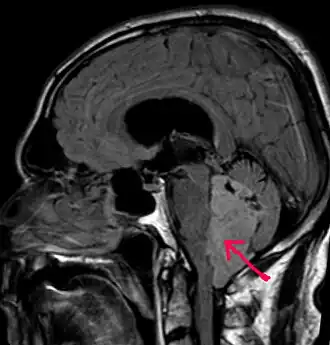

В типичных случаях на МРТ эпендимомы видны в виде объёмных образований, которые заполняют, а иногда и полностью тампонируют полость IV желудочка и распространяются в большую затылочную цистерну или боковую цистерну моста. Солидная часть новообразования на Т1-взвешенных томограммах выглядит изо- или даже гипоинтенсивной и гиперинтенсивной на Т2-взвешенных томограммах[24].

Дифференциальная диагностика эпендимом с другими глиомами основывается в основном на их локализации и топографии, а не на различиях интенсивности сигнала или степени контрастного усиления[25]. Кистозный компонент имеет гипоинтенсивный сигнал на Т1-взвешенных МРТ и гиперинтенсивный по отношению к мозгу на изображениях, взвешенных по Т2. Гетерогенность структуры опухоли обусловлена наличием кист, петрификатов, опухолевой сосудистой сети. После введения контраста отмечается негомогенное усиление средней интенсивности[26]. Дифференциальную диагностику эпендимом боковых желудочков необходимо проводить с медуллобластомами и астроцитомами[23].

Целью операции является максимальное удаление внутричерепной части опухоли с тем, чтобы у больного не возник неврологический дефицит. Если эпендимома прорастает в дно IV желудочка, что отмечается в 50 % случаев[35], её тотальное удаление становится невозможным. После операции ликвор отправляют на цитологическое исследование с целью определить наличие и количество в нём опухолевых клеток. Доступ к образованиям IV желудочка осуществляется путём срединного субокципитального доступа[3].